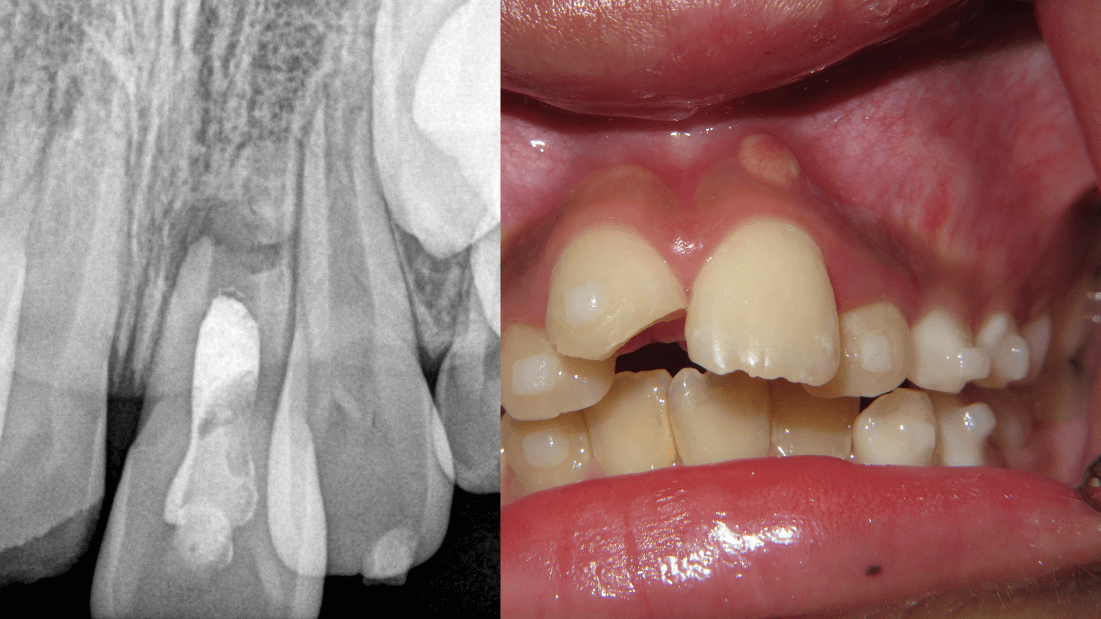

9-year old boy presents with a chronic apical abscess, after a failing attempt for pulp regeneration.